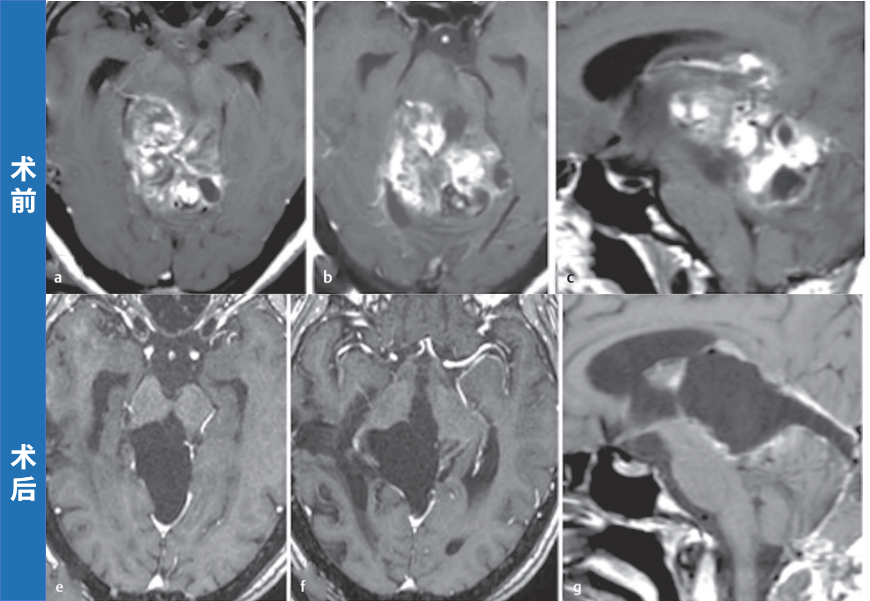

案例三:中脑胶质瘤,术后9年无复发

患者为30岁女性,脑干胶质瘤。最初接受了立体定向下囊肿抽吸术和放疗,病理诊断为毛细胞型星形细胞瘤,但肿瘤仍在继续生长。巴特朗菲教授全切手术后,随访头颅MRI显示9年内无任何肿瘤复发迹象。